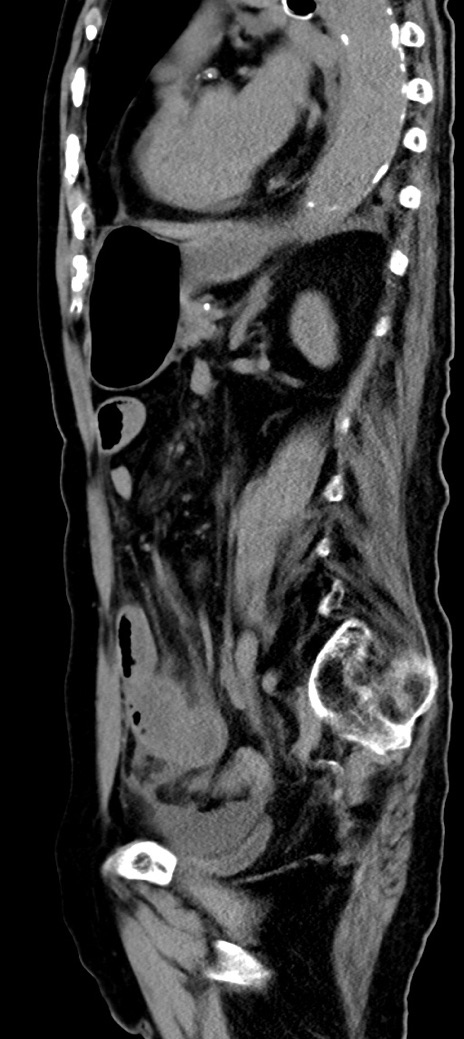

症例40(矢状断像)他院1日前

【症例】90歳代女性

【主訴】腹痛・嘔吐

【現病歴】 食欲低下、嘔吐があり昨日他院受診。肺炎と診断され入院となる。入院後より腹部全体に圧痛あり。胃管留置され経過みていたが、症状持続するため、

当院転院となる。

【既往歴】胸椎圧迫骨折、胆石症

【身体所見】腹部:中央に激痛あり、圧痛あり、反跳痛不明

【データ】WBC 17100、CRP 18.82